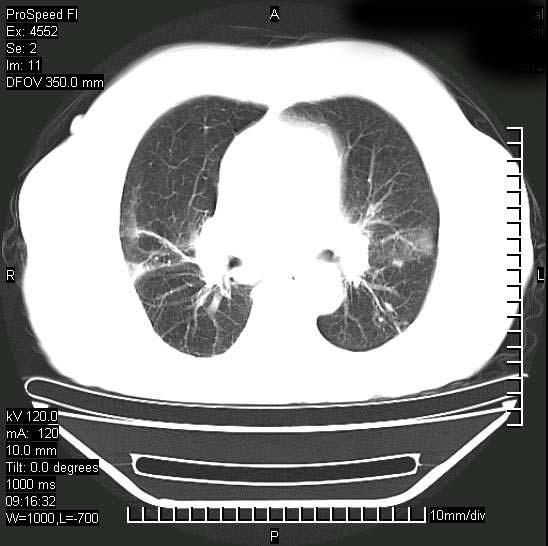

标题: CT15528:女性,79岁,近几日晚上高热,39度,仍咳少量血

十几年前曾患肺结核,一周前突咳血约100ml,中性粒细胞稍高,诊断两上肺陈旧结核,下肺炎症,给予抗炎治疗,近几日晚上高热,39度,仍咳少量血,4天前ct及今天ct上传。

[face=黑体]8月30日[/face]